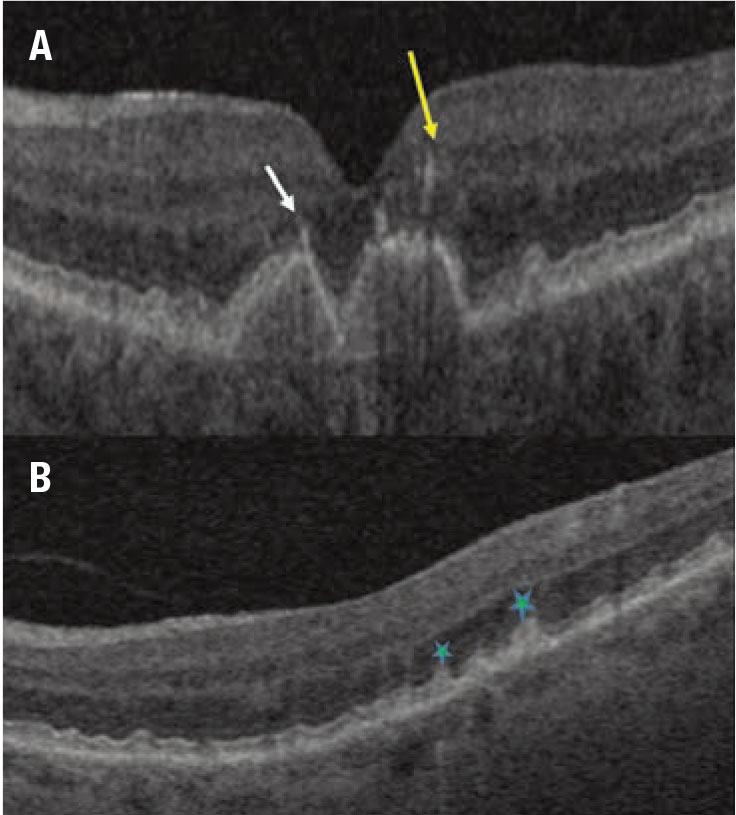

Figure 2. Examples of qualitative optical coherence tomography biomarkers in dry age-related macular degeneration. A) A horizontal spectral-domain OCT B-scan slice through the macula shows confluent hyperreflective foci over the drusenoid pigment epithelial detachment (arrows). B) Horizontal SD-OCT scans demonstrate subretinal drusenoid deposits (stars). |

Researchers have evaluated nonexudative age-related macular degeneration extensively for various imaging biomarkers. Qualitative features on SD-OCT that have been associated with progression to advanced AMD include intraretinal hyper-reflective foci (IHRF), complex drusenoid lesions (DL, i.e., heterogeneity of reflectivity), subretinal drusenoid deposits (SDD) and drusen burden (Figure 2).9

In fact, these qualitative features have demonstrated the following hazard ratios (HR) for developing late AMD:

- 5.21 for IHRF (95% confidence interval [CI], 3.29-8.26);

- 2.42 for hyporeflective foci (hRF) within DLs (95%CI, 1.74-3.38);

- 1.95 for SDD (95% CI, 1.34-2.82); and

- 1.46 for large drusen volume (95% CI, 1.03-2.07).10